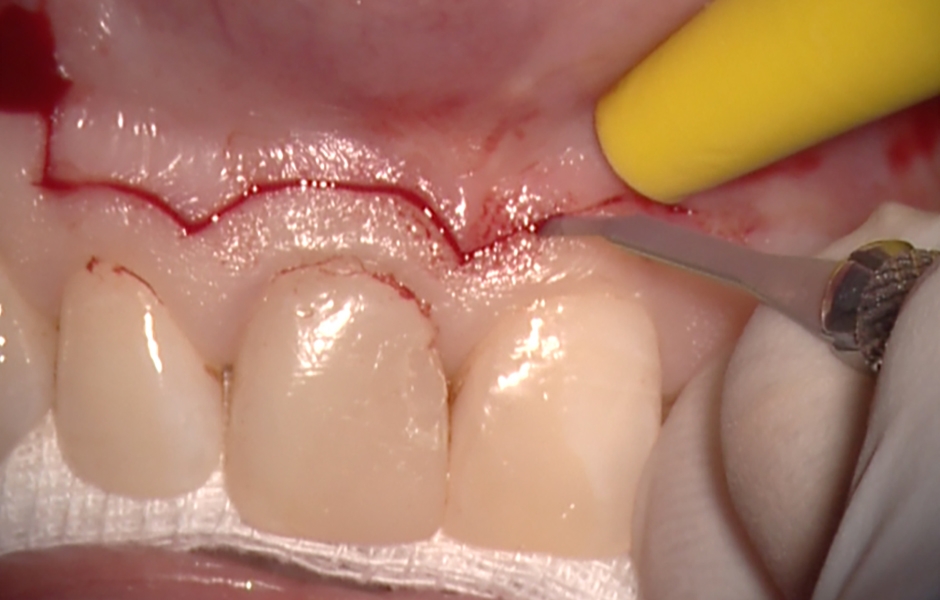

Obr. 1.2: Submarginální incize.